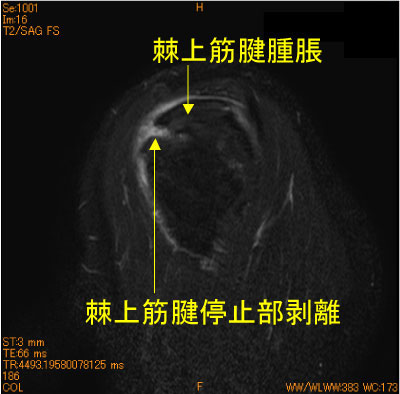

50代男性。スキーで転倒後9日後MRI。スキー歴40年。

棘上筋腱停止部の大結節superior facetからの剥離を認める。

![]() Obl. Sag T2WI 脂肪抑制 |